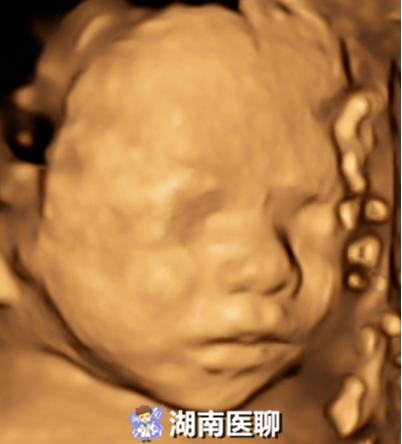

三维:同时具备上下、左右、前后三个方向,这样就有空间位置了,形成了人的视觉立体感。胎儿三维彩超就是利用超声仪器上的三维成像技术对胎儿特定部位进行成像处理,就形成了一幅幅很有立体感的胎儿图像: